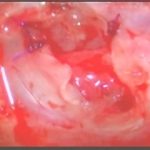

手術前1

摘出 前

摘出 中